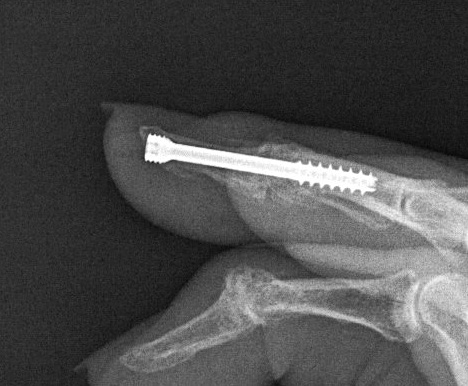

DIPJ Arthrodesis

Position

- 15 - 20o flexion

A. Headless compression screw